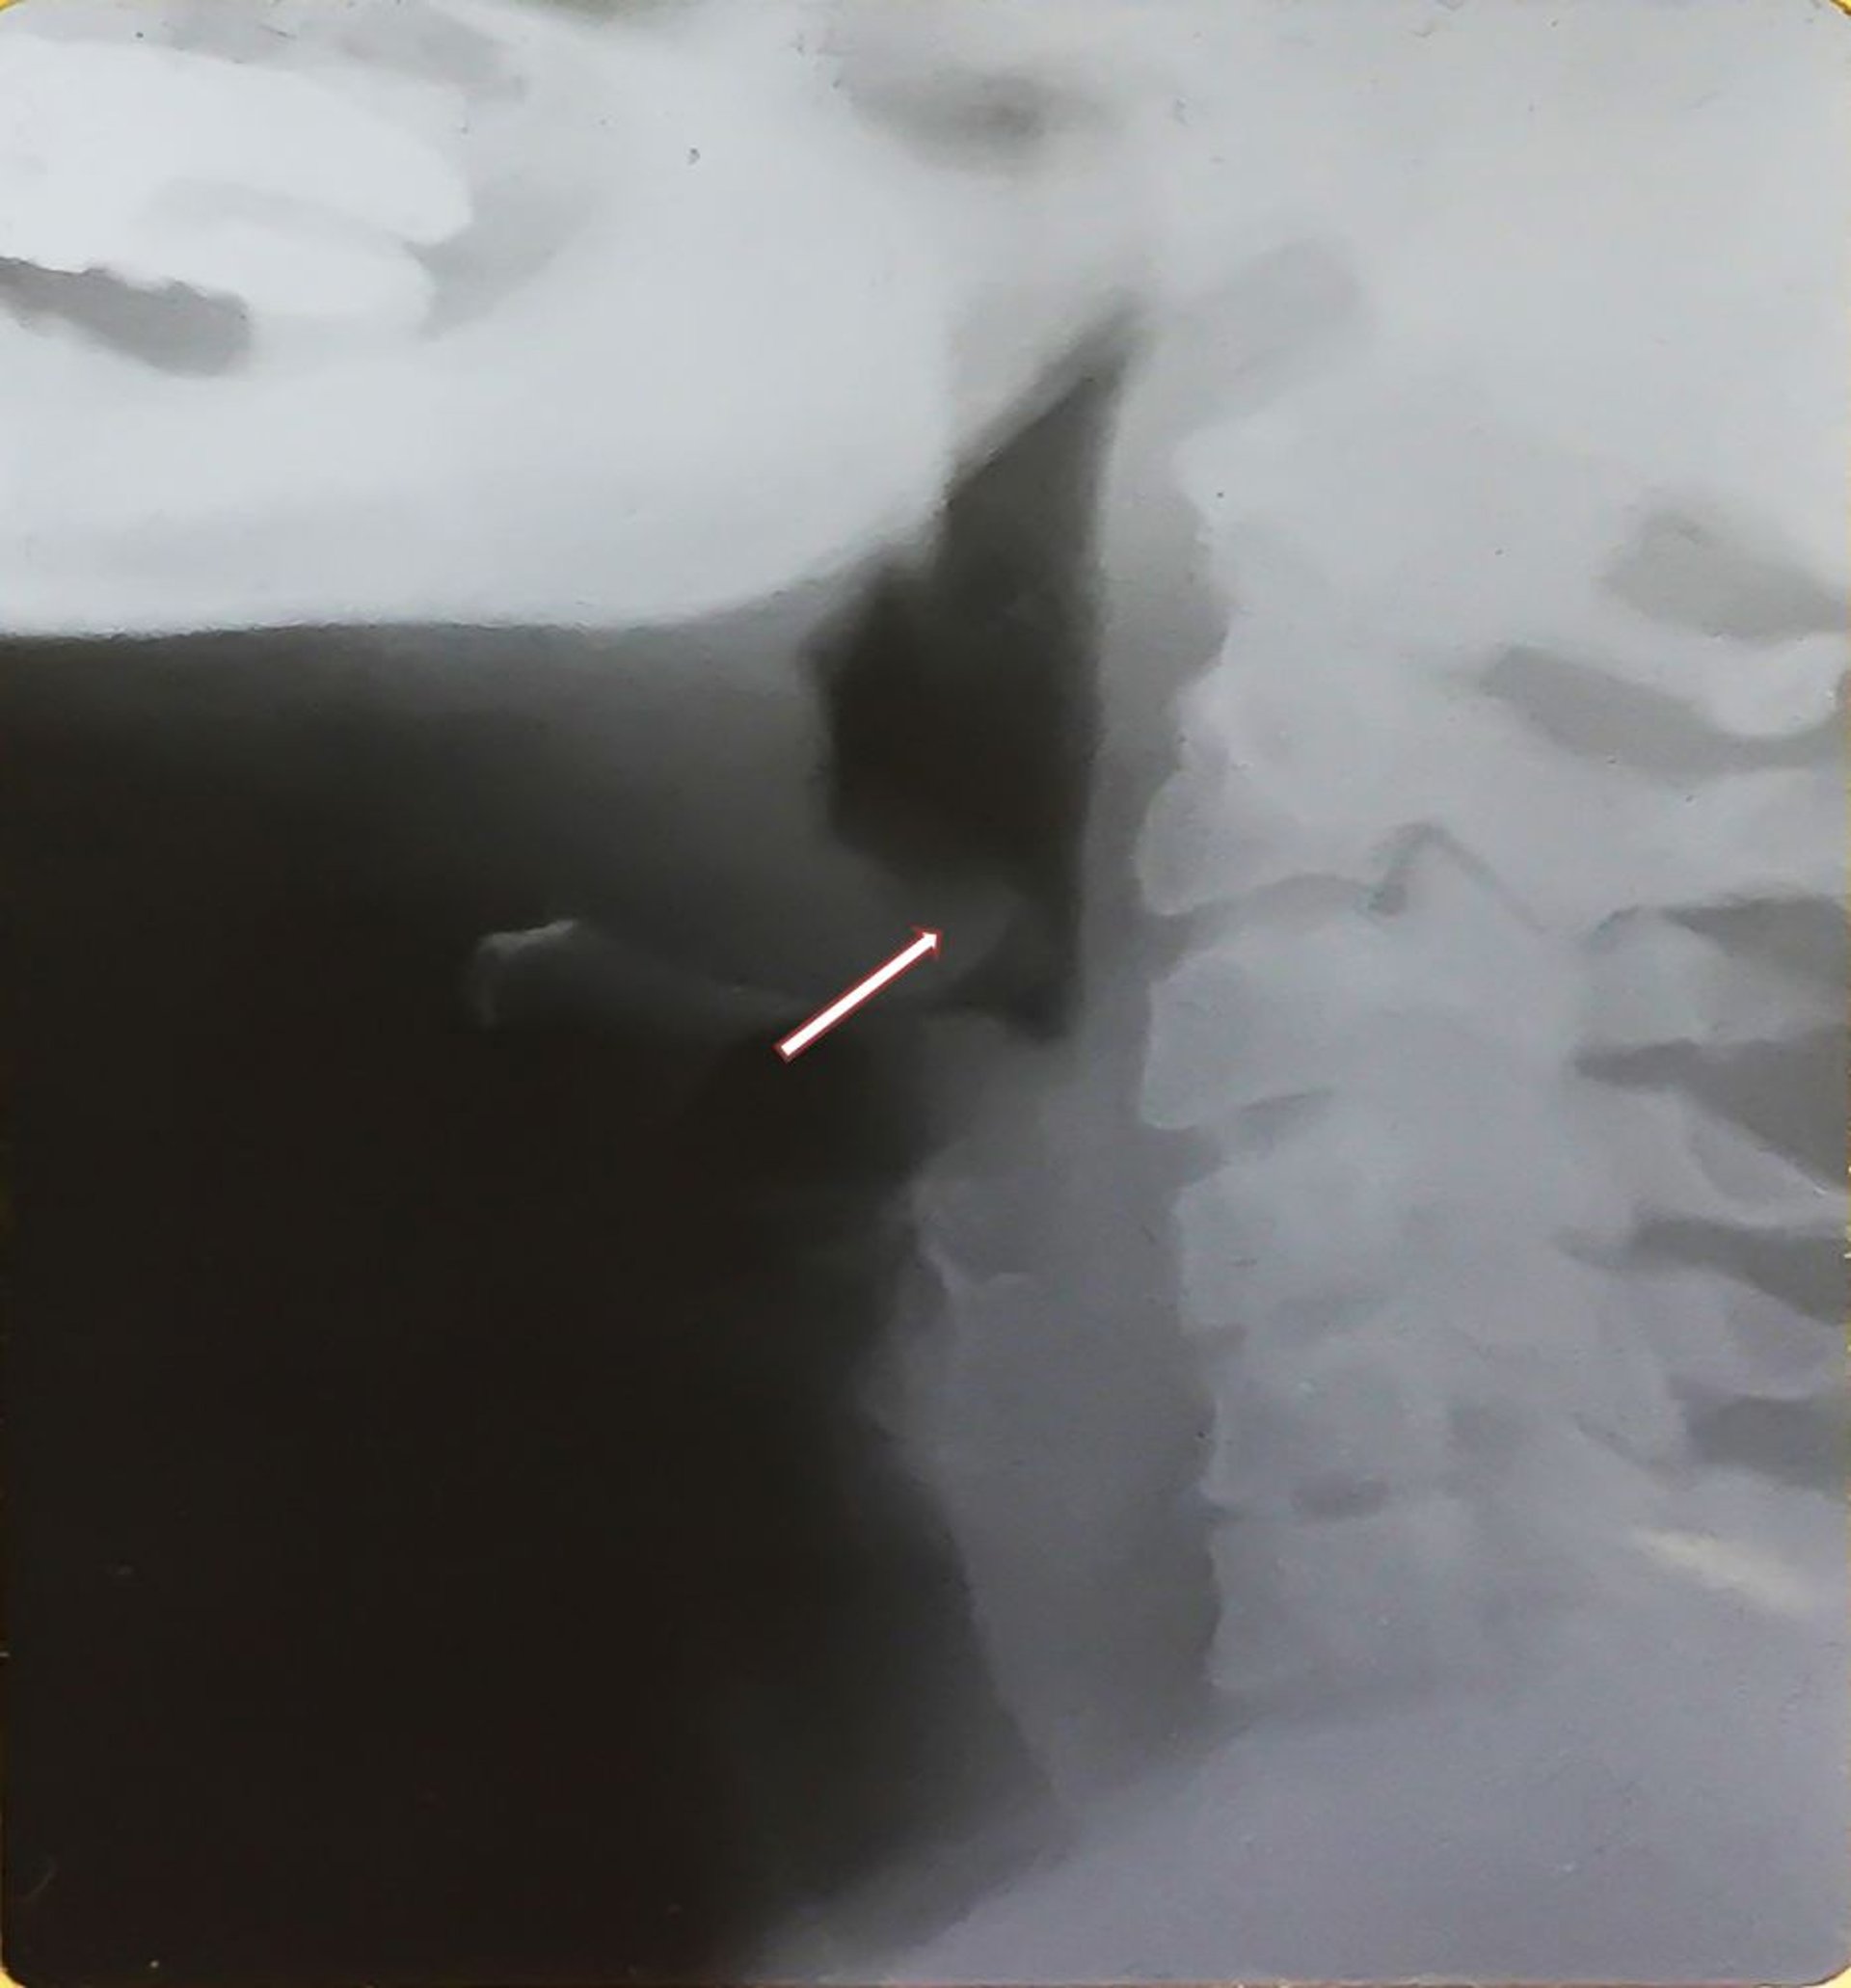

Epiglottite (adulto)

Questa radiografia mostra l'epiglottide ingrandita (segno del pollice, vedi freccia) caratteristica dell'epiglottite e della distensione dell'ipofaringe. Si noti l'epiglottide ispessita, dislocata posteriormente.

Image provided by Clarence T. Sasaki, MD.